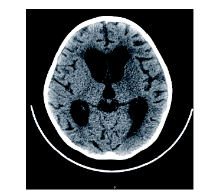

周正根(影像科主治医师):根据患儿的影像学图片介绍一下TBM的影像学特点, 首先, TBM比较容易出现脑积水, 见图1, 在脑底部的脑池可见分泌物, 脑室壁增厚; 其次, 脑室、脑沟可见到钙化, 见图2和图3, 钙化灶对结核的诊断有一定意义; 第三, 由于TBM可能侵犯到小血管, 所以可以见到一些低密度的梗塞病灶。